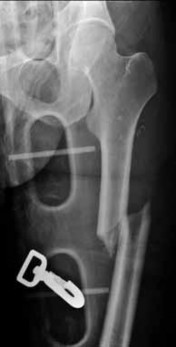

A 12-year-old obese male presents with left thigh pain and a limp. The provided radiograph is shown.

He is diagnosed with a Slipped Capital Femoral Epiphysis (SCFE). What is the most widely accepted indication for prophylactic pinning of the contralateral hip?

Explanation

Prophylactic pinning of the contralateral hip is generally indicated in patients with metabolic or endocrine disorders (e.g., hypothyroidism, renal osteodystrophy) and in patients presenting at a very young age (girls <10, boys <12) due to a substantially increased risk of a contralateral slip. Recent literature also strongly weights the modified Oxford bone age score.